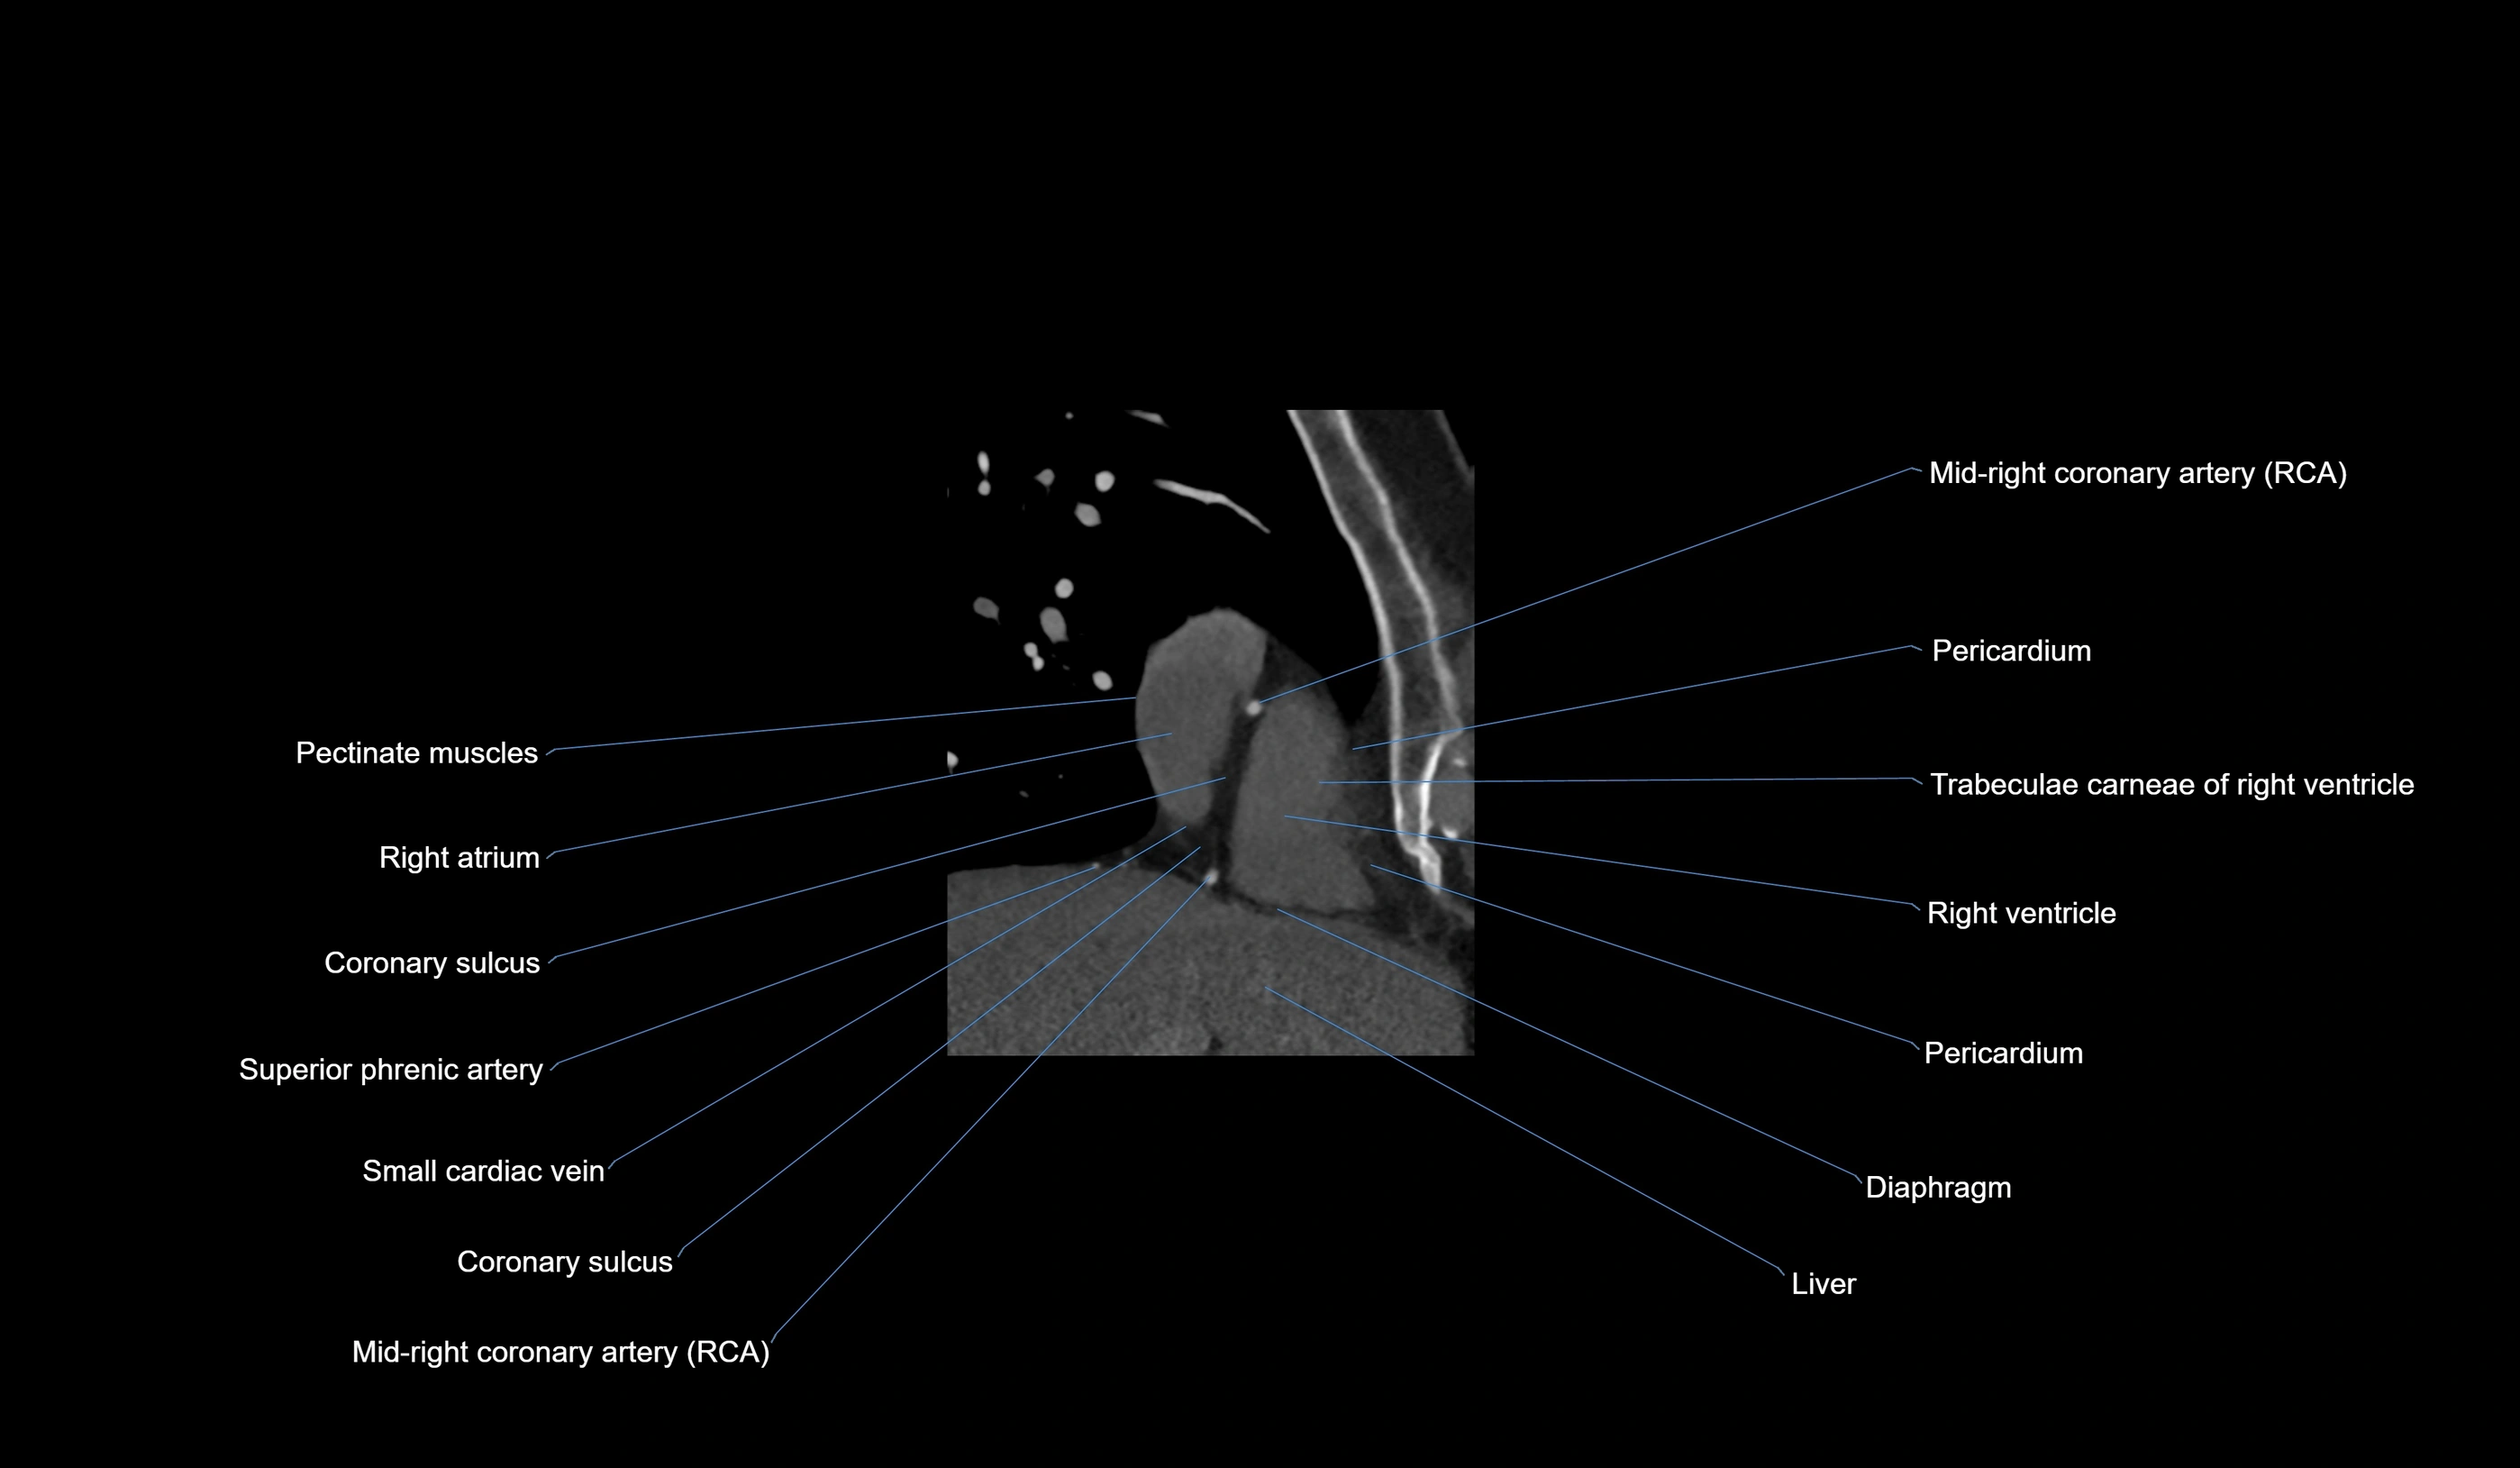

CT images